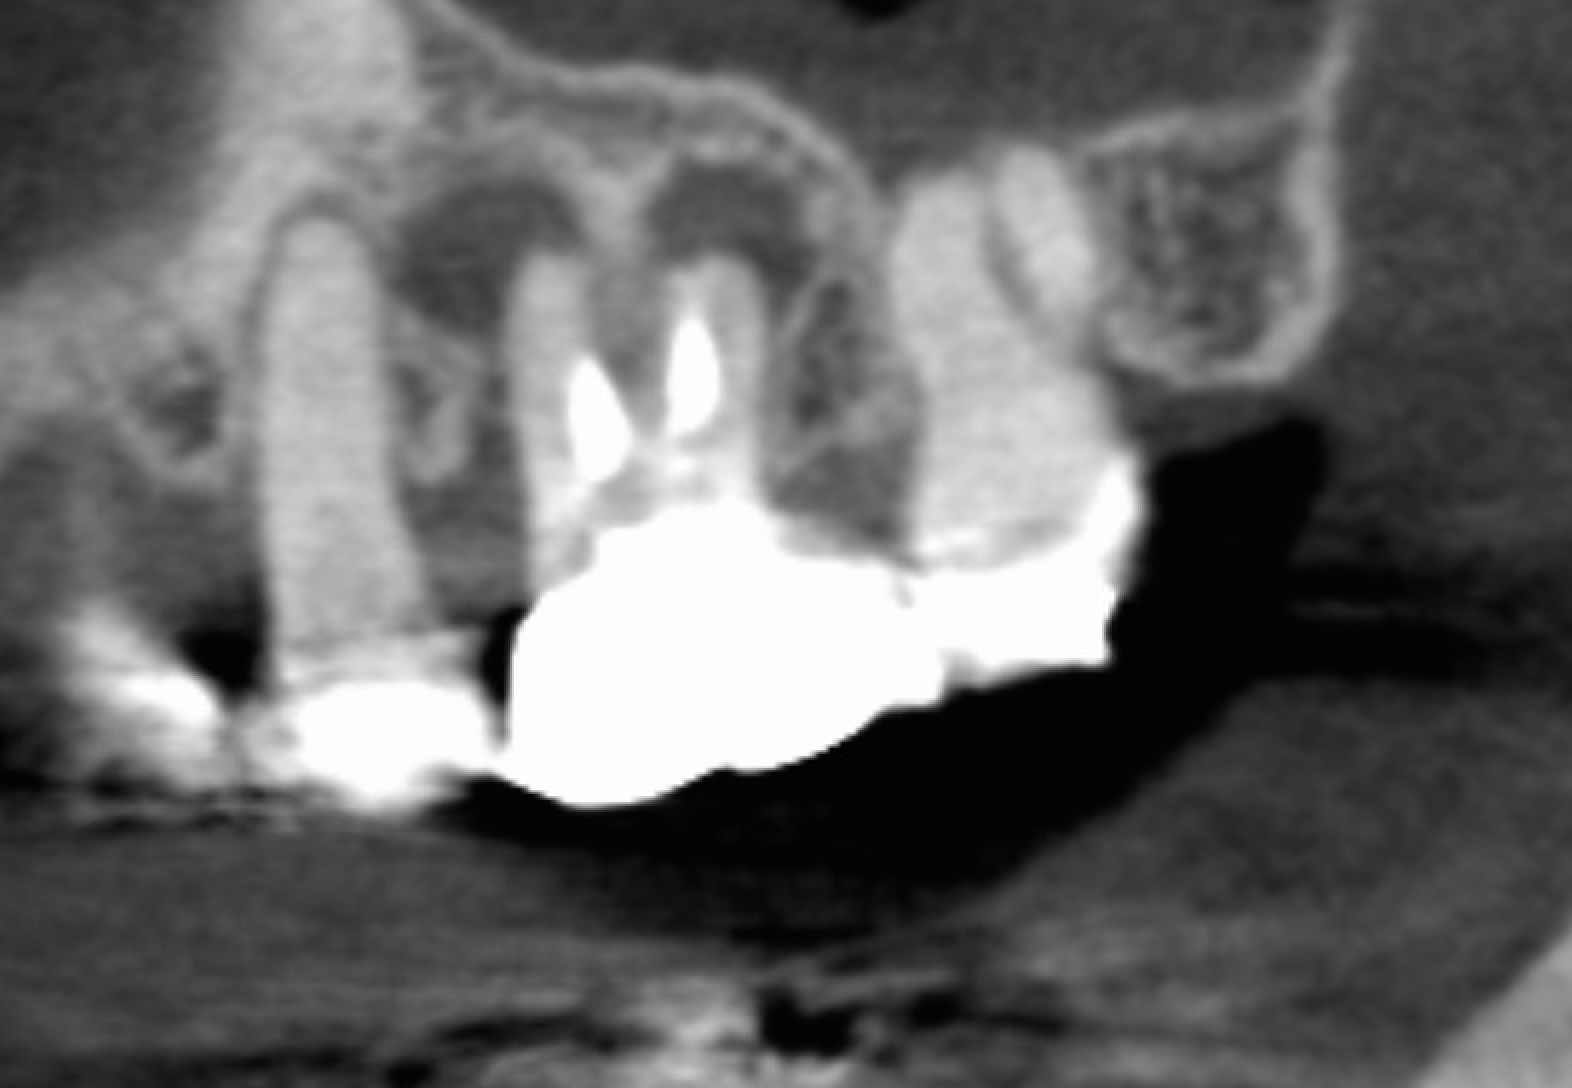

一般的なレントゲンでは、歯や骨が重なって写るため、原因がはっきりしないことがあります。

当院では必要に応じて歯科用CTを用い、骨の厚みや感染の広がり、根の形態を三次元的に確認します。

根管治療領域では、CTで破折の間接所見や骨欠損の形態を三次元で確認できる点などが解説されています。

たとえば、以下のようなことが分かる場合があります。

未処置の根管(見落とされていた根)が疑われる

骨の状態(量・形)が想定と違う

歯ぐき/歯周病由来の問題が関係している可能性がある